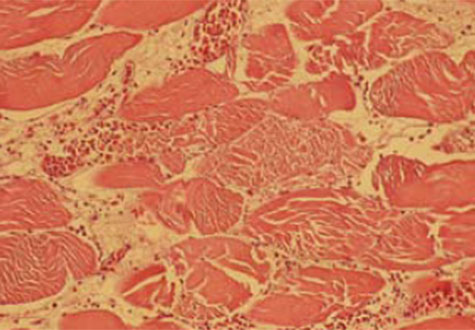

8.- Hialinización (necrosis de Zenker) y lesiones necrobióticas degenerativas severas del músculo estriado. Grupos de heterófilos y macrófagos rodeando las áreas necróticas. El diagnóstico está basado en la historia, signos clínicos y lesiones macroscópicas y microscópicas. El diagnóstico diferencial se realiza con botulismo y deficiencia de vitamina E y selenio.